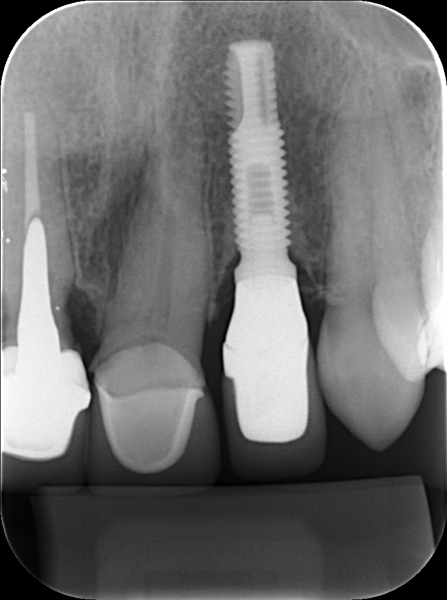

Radiografia Periapical